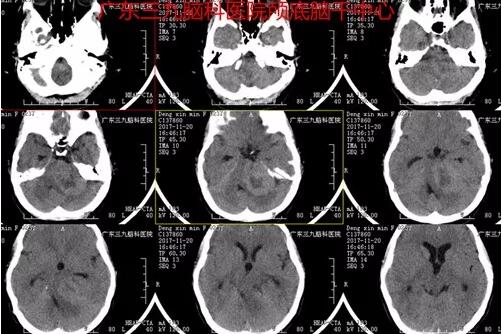

图1:2017-11-20 头颅CT示左侧桥小脑角区示一团片状稍高、低混杂密度影,邻近左侧听神经孔增宽